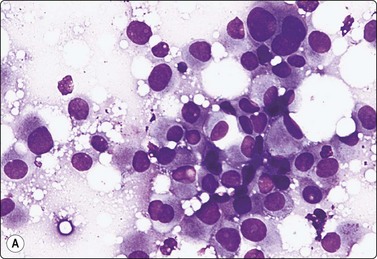

image image

Fig. 7.1 Radiation-induced atypia

(A) The epithelial cells in this irregular cluster show considerable nuclear enlargement, pleomorphism and hyperchromasia, but also some degenerative changes such as loss of nuclear structure (MGG, HP); (B) Corresponding tissue section (H&E, IP).